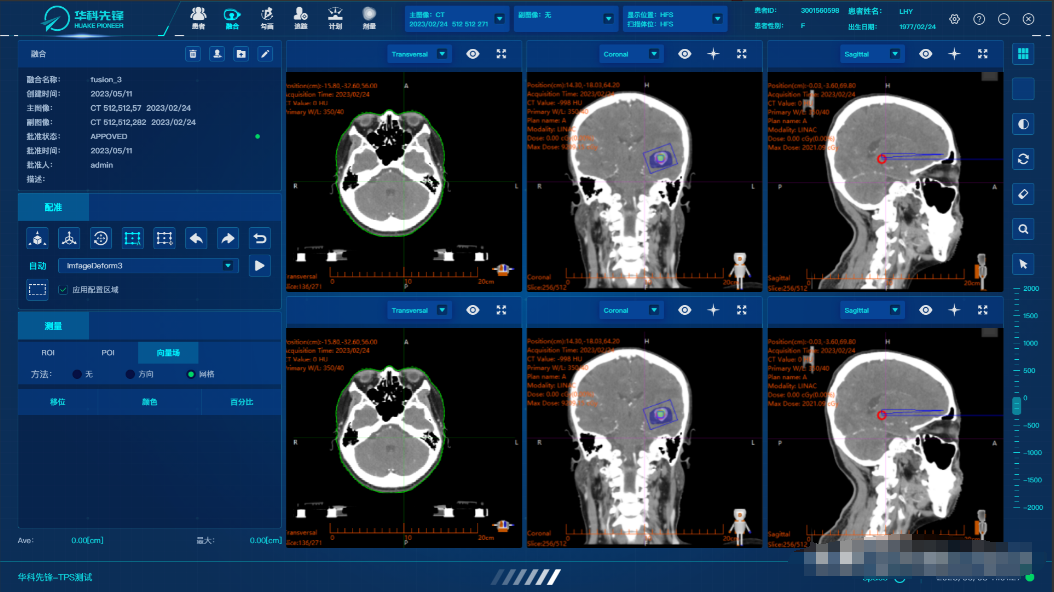

三、医学影像存档与通信系统(PACS)的作用

医学影像存档与通信系统(PACS)是专门用于医学影像管理的系统,它可以实现医学影像的采集、存储、传输、显示和处理等功能。

在影像采集方面,PACS 系统可以与各种医学影像设备进行连接,如 CT、MRI、超声等,实现影像的自动采集和传输。在影像存储方面,系统可以将采集到的影像存储在服务器中,实现长期保存和管理。在影像传输方面,系统可以通过网络将影像传输到医生工作站、手术室、会诊室等,方便医生进行诊断和治疗。在影像显示方面,系统可以提供高清晰度的影像显示功能,方便医生进行观察和分析。在影像处理方面,系统可以对影像进行各种处理,如增强、滤波、测量等,为医生提供更多的诊断信息。

PACS 系统的作用主要体现在以下几个方面:首先,提高了影像诊断的效率和准确性。医生可以通过系统快速查看影像信息,避免了传统胶片的繁琐和错误。同时,系统还可以提供影像对比、三维重建等功能,帮助医生更好地进行诊断。其次,方便了影像的存储和管理。影像可以存储在服务器中,不会因为时间和空间的限制而丢失。同时,系统还可以对影像进行分类、归档等管理,方便查询和使用。再次,促进了医疗信息的共享和交流。PACS 系统可以与其他医疗信息系统进行对接,实现医疗信息的共享和交流。医生可以通过系统查看患者的病历记录、检查检验报告等,为诊断和治疗提供参考。最后,有助于医疗质量的控制和管理。PACS 系统可以对影像的质量、诊断的准确性等进行监控和管理,提高医疗质量和安全。